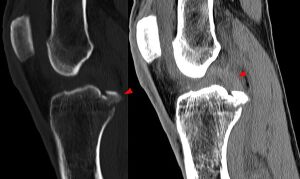

Röntgenbild: Kreuzbandriss - Hellerhoff commons.wikimedia.org, CC BY-SA 3.0

Bei einem Bänderriss reißen gelenkstabilisierende Bänder oft komplett ab. Als Folge können weitere Gelenkschäden (zB Meniskusverletzungen) entstehen.

Bei einigen Komplettabrissen (zB Kreuzbänder oder Bandverletzungen in der Schulter) wird häufig operativ behandelt.